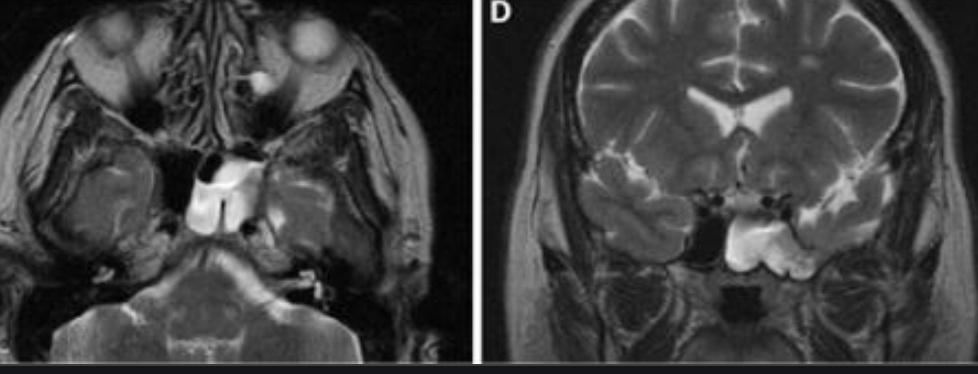

Ecchordosis Physaliphora

Cystic lesion in the prepontine cistern without enhancement or restricted diffusion extending into bone.

Absence of enhancement or restricted diffusion together with non-aggressive bony margins in this location is typical of a retroclival ecchordosis physaliphora, a notochord remnant.

Ecchordosis physaliphora is a congenital benign hamartomatous lesion derived from notochord remnants, usually located in the retroclival prepontine region, but can be found anywhere from the skull base to the sacrum.

Unlike chordomas which are often symptomatic due to brainstem or cranial nerve compression, patients with ecchordosis physaliphora are usually asymptomatic. They are found in ~2% of autopsies 1.

Ecchordosis physaliphora arise from remaining notochord cells along the axis of the spine after embryogenesis. Unfortunately, ecchordosis physaliphora and chordoma are histologically indistinguishable, other than by examining the margins, the latter demonstrating infiltrative growth.